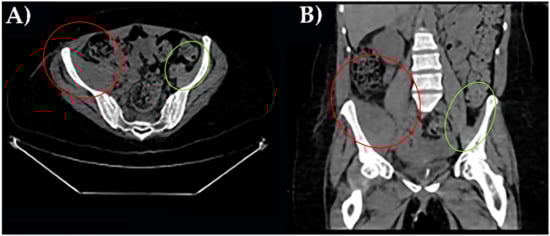

Three different instrumental imaging examinations were performed. An ultrasound study excluded a peritoneal effusion but was not more informative for extensive meteorism. CT without contrast revealed an enlargement of right iliac muscle, slightly parenchymal inhomogeneity without signs of overt bleeding and excluded other causes of leg pain (Figure 1).

Figure 1. CT axial scan of the pelvis with right ileal muscle hematoma. (A). CT coronal scan of the pelvis with right ileal muscle hematoma (B). In red, pathological finding; in green, normal appearance.